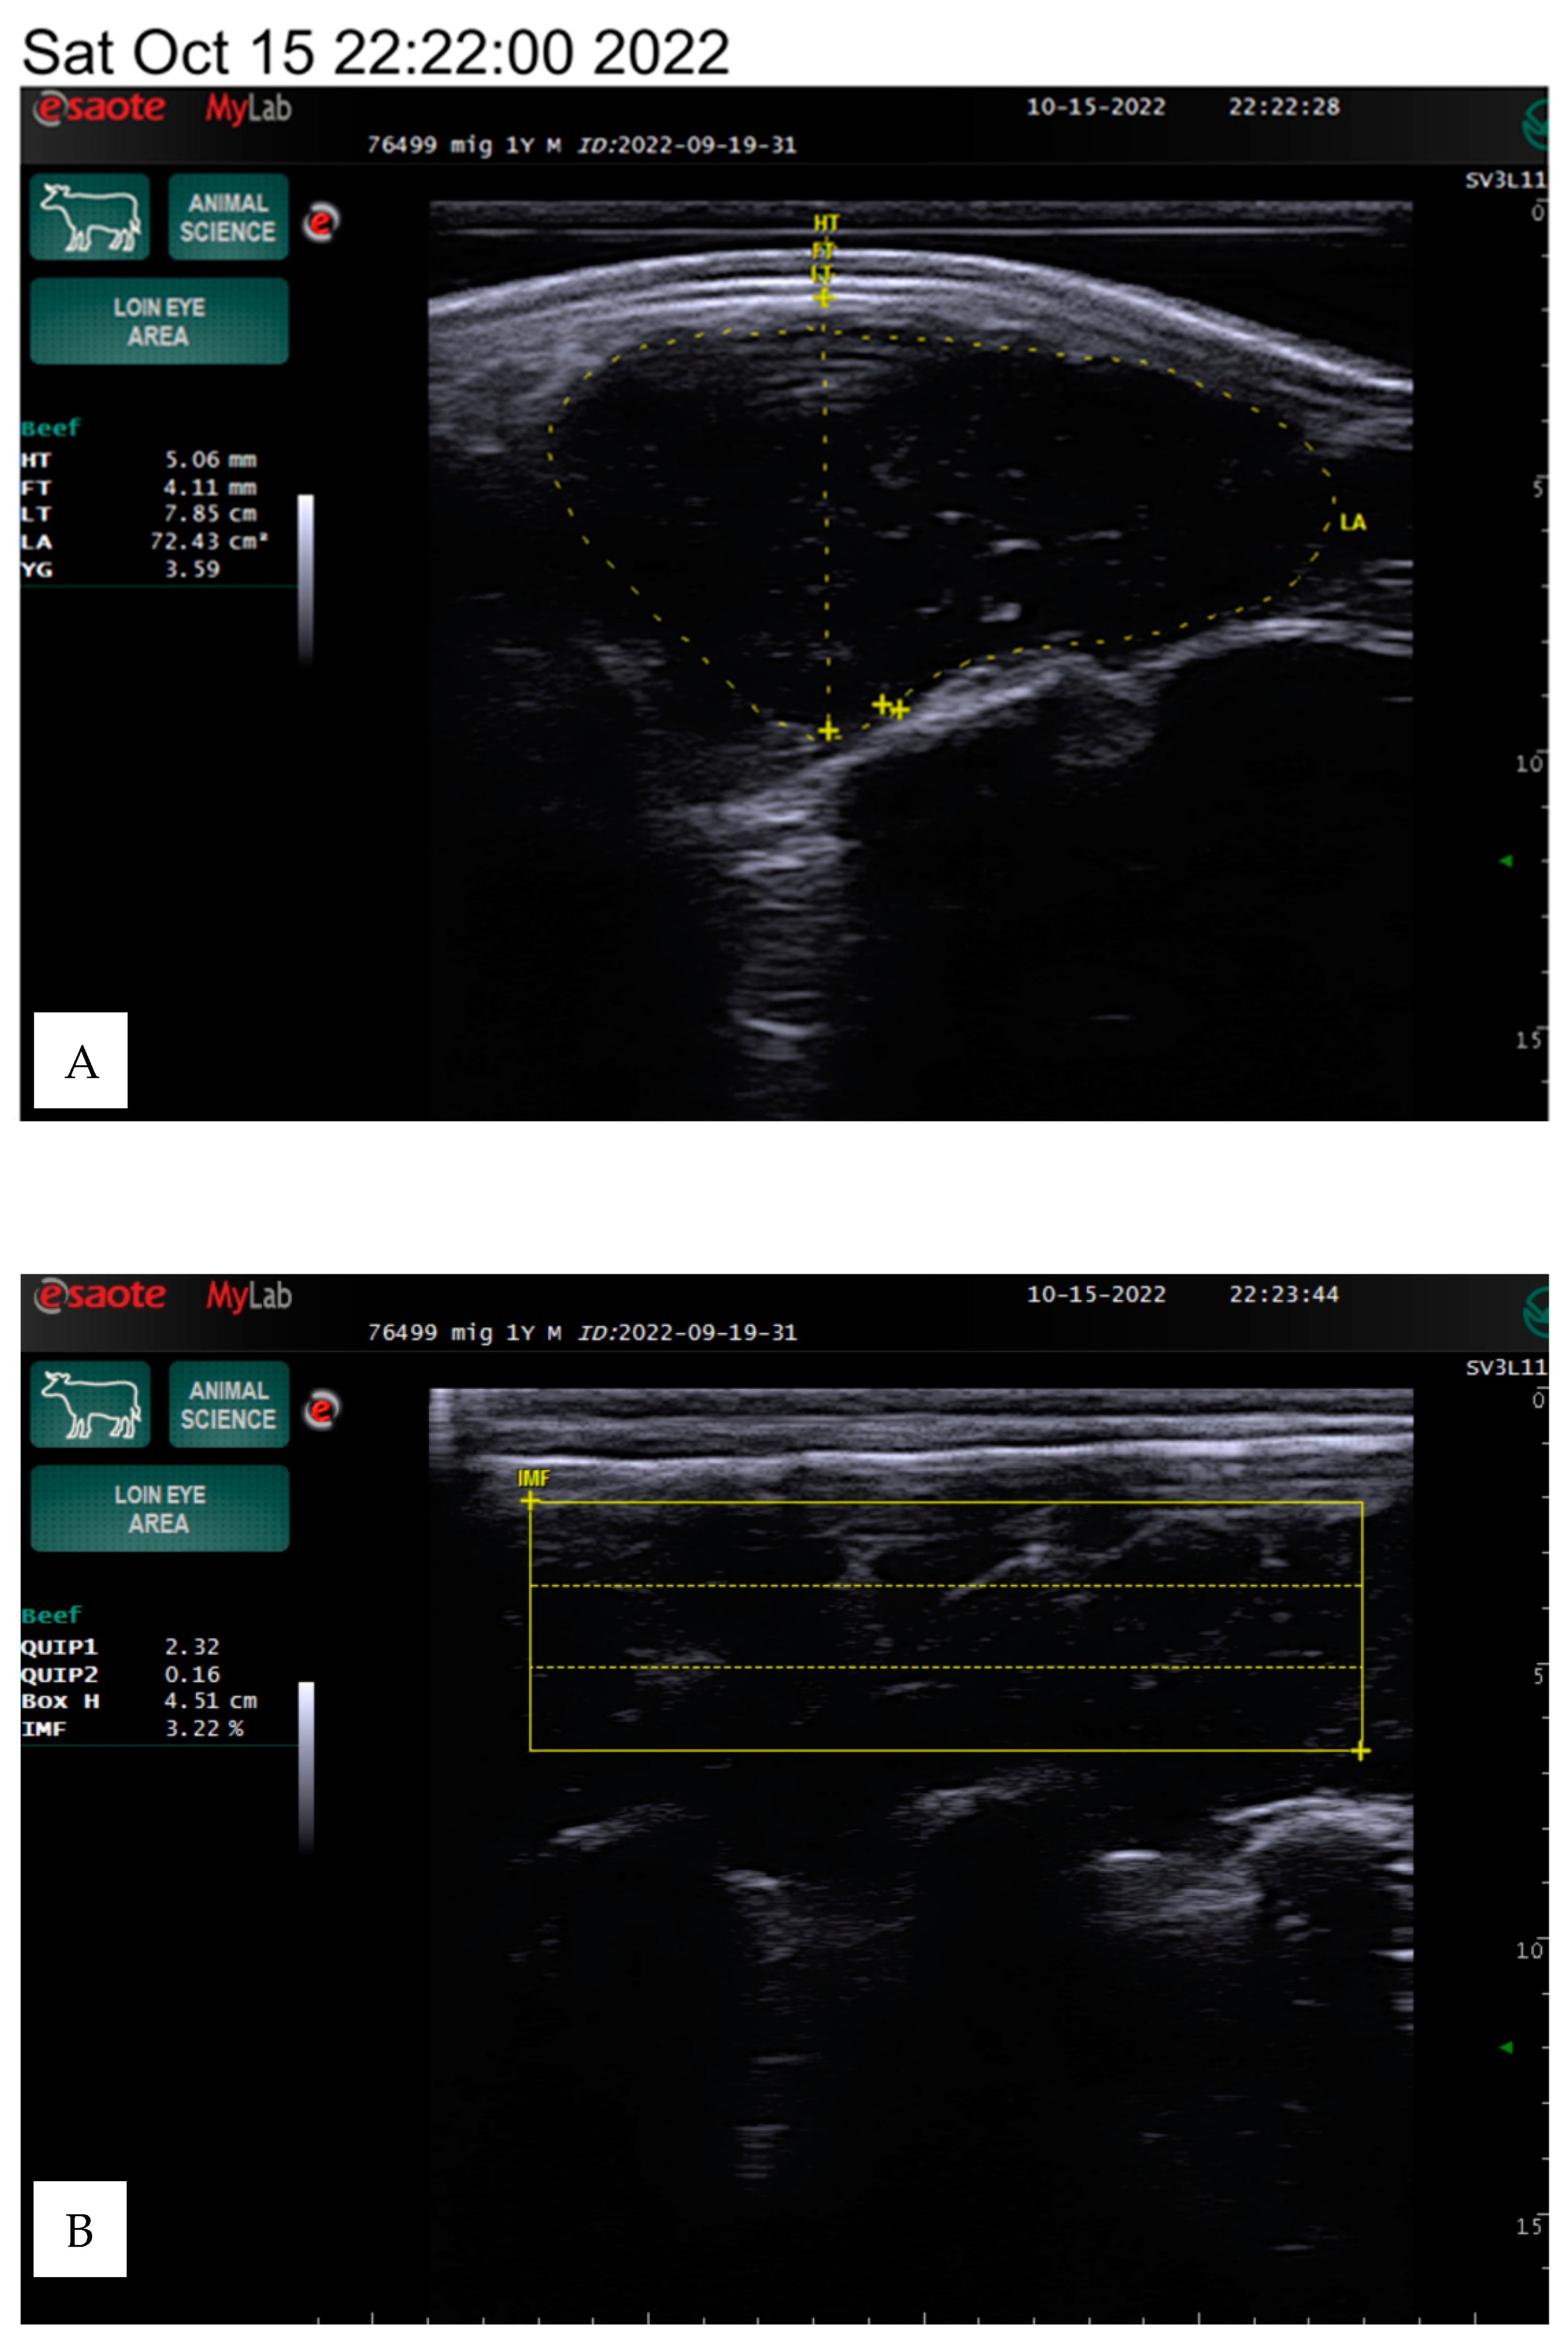

The animals were kept under the same conditions and were fed a total mixed ration based on a weight range of 350–600 kg. The ration primarily consisted of 3.5–6 kg of concentrates (barley, maize, oats, peas, and wheat) and 10–20 kg of grass hay, with a protein content of 226–426 g and a dry matter content of 7.21–13.56 kg. The carcass quality indicators were estimated on live animals using an ultrasound linear transducer using a silicone sleeve for the loin eye area with a frequency range of 4.5 to 6.5 MHz and a depth of 8.8 to 13 cm on the 12th and 13th ribs, following the methodology of Silva et al. [13], as presented in Figure 1.

Figure 1.

The example ultrasound images of the longissimus dorsi muscle of the Angus bulls, weights of 782 kg, IF 3.59% (A,B) and 485 kg, IF 8.19% (B,D). HT—hide thickness, FT—fat thickness (mm), LT—loin thickness (cm), LA—loin area (cm2), YG—yield grade, BH—box height (cm), IF—intramuscular fat (%).

The area of the longissimus dorsi was measured in square centimeters between the 12th and 13th ribs by determining the perimeter of the cross-sectional image displayed on the screen (Figure 1). The longissimus dorsi muscle is a value of the ratio of muscle to lean product of the animal. Backfat thickness is one of the major quantitative traits that affects carcass quality in beef cattle and has been used to predict carcass retail yield components in live animals. The amount of intramuscular fat determines the indicator, known as marbling.

The evaluation parameters included body weight, hide thickness, fat thickness, loin thickness, loin area, yield grade, box height, and intramuscular fat percentage, which we determined using the Measure mode in the ultrasound program. The box height depends on the screen image and the size of the intercostal area, so the data may vary between animals, as shown in Figure 1.